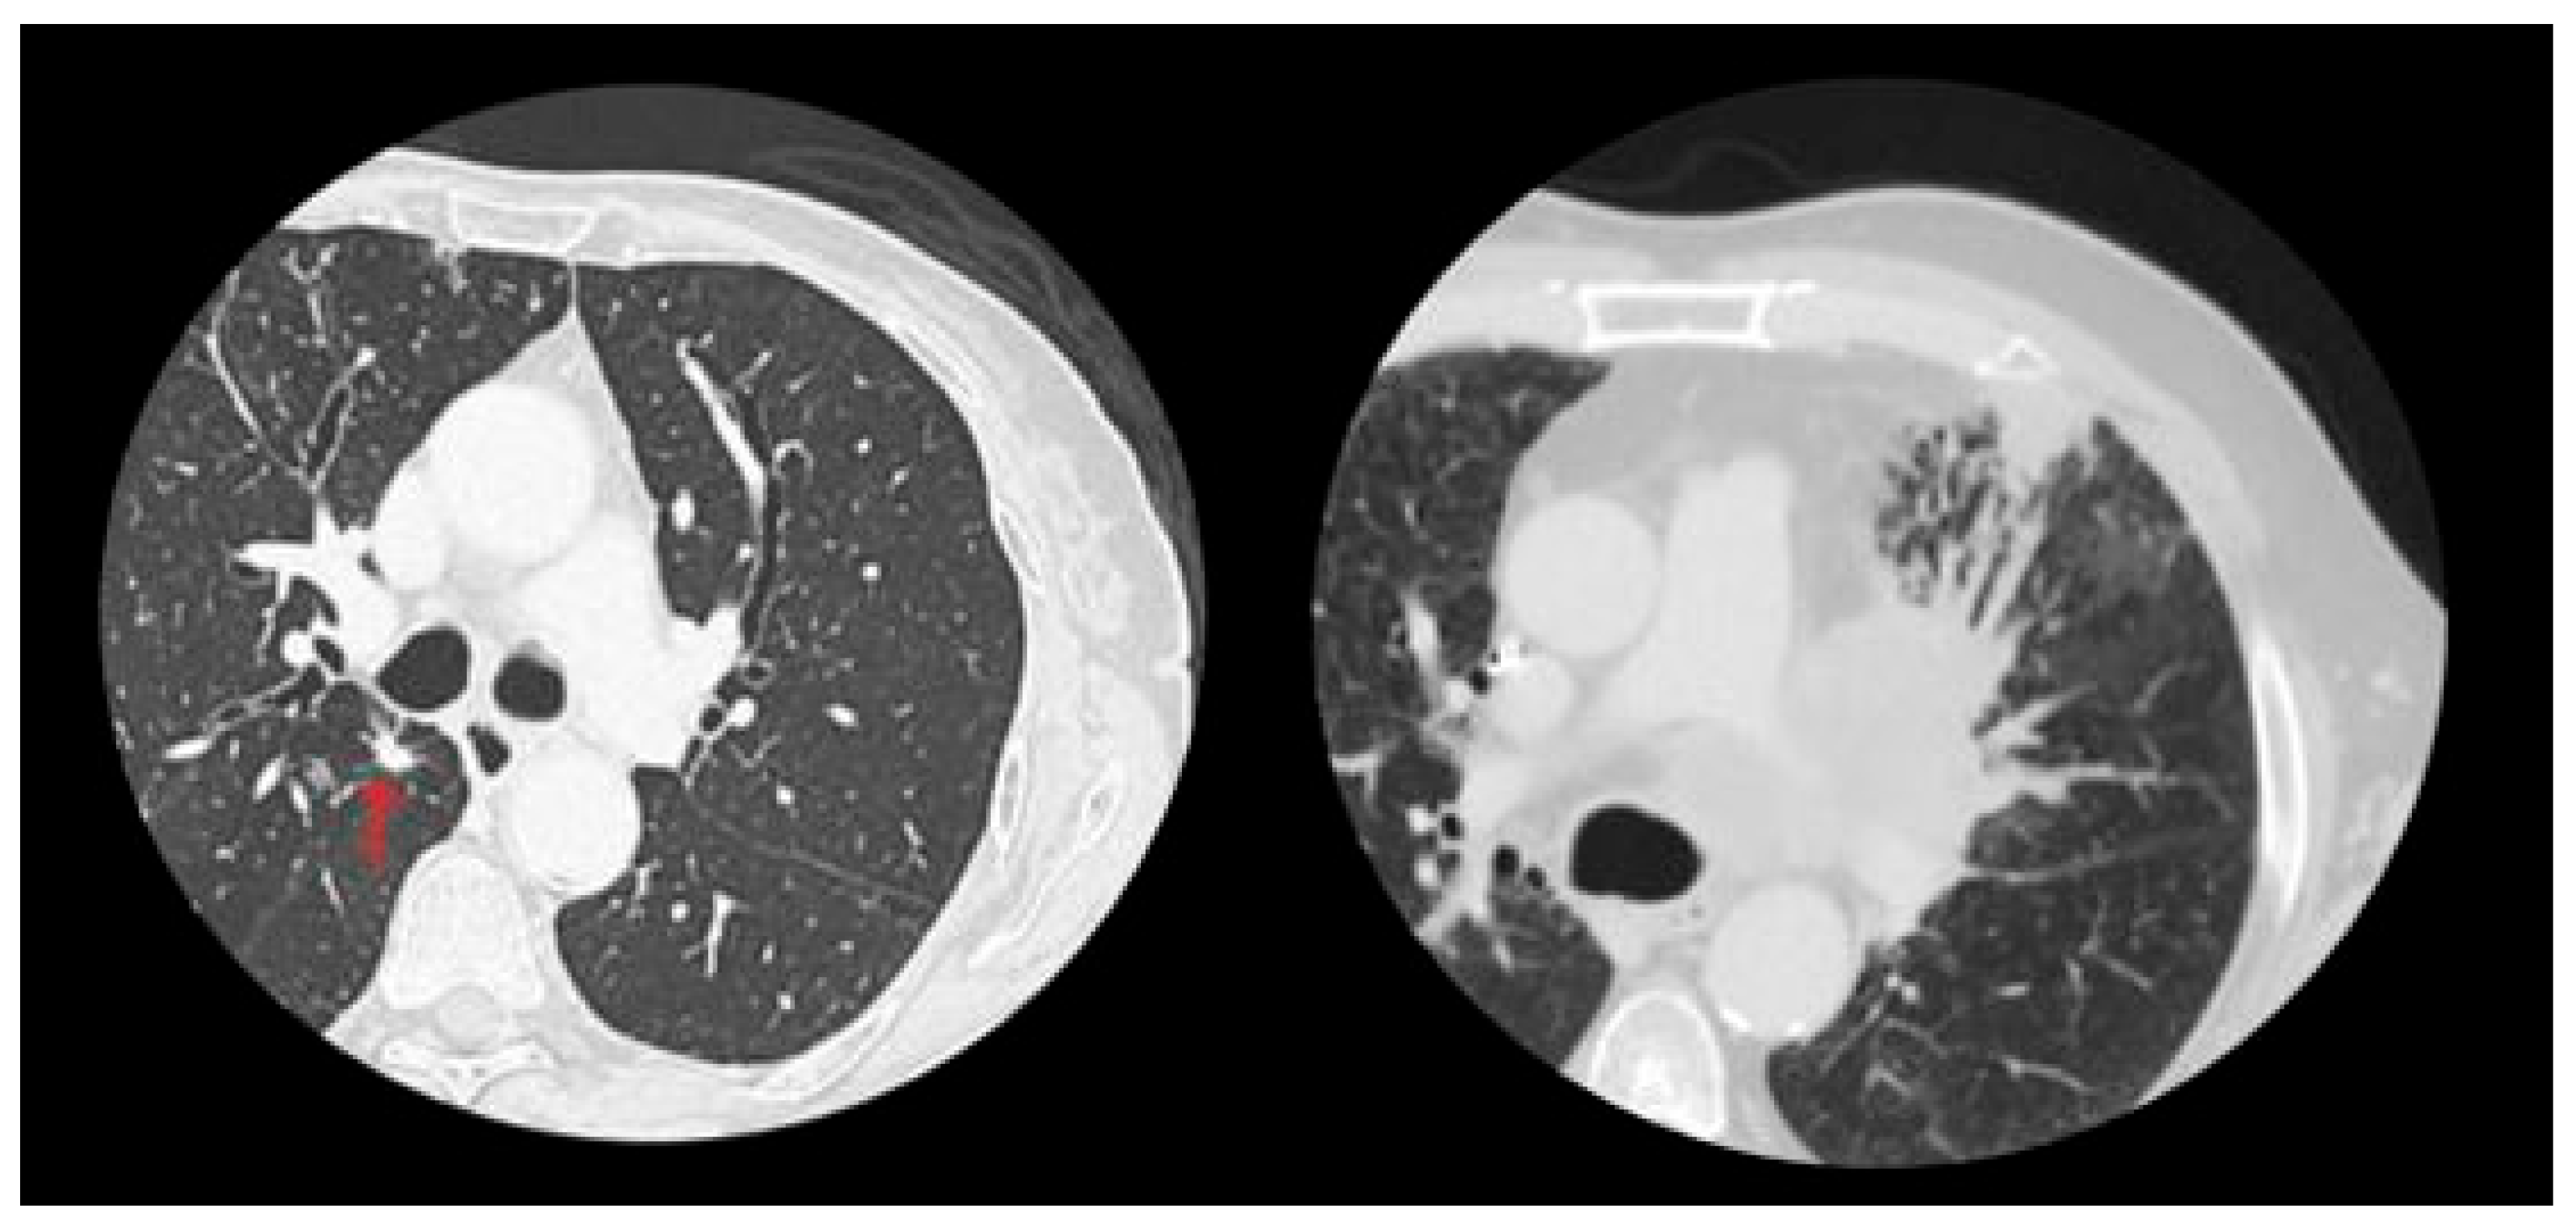

- Pulmonary Micronodules: Small nodular lesions, typically under 10 mm in diameter, were observed within the lung parenchyma. While these findings are often benign, they may require follow-up imaging to rule out early-stage neoplastic processes (Figure 2).